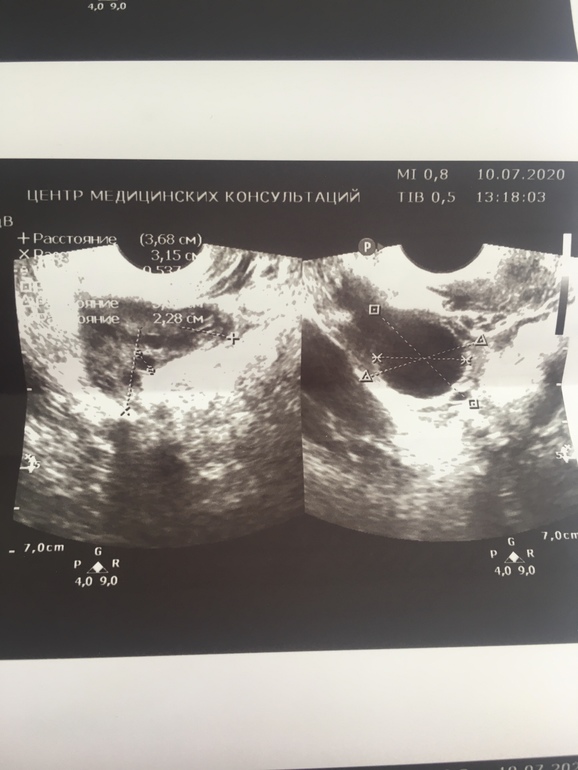

Желтое тело

Была на узи, 21дц, овуля была(я в шоке, с моим длинным циклом), жидкость есть

Единственное, врачу не понравилось ЖТ, рекомендовала сдать прог и (скорее всего) утрик

На фото вроде как не ЖТ🧐

А не понравилось что? Размер или что?

А что это может быть?🤨

Не понравился плохой кровоток в нем(???)

Как-то не похоже на ЖТ, у него края обычно не ровные и выглядит оно немного по-другому.

Блин, она говорила, что это жт

Я не знаю, как оно выглядит...